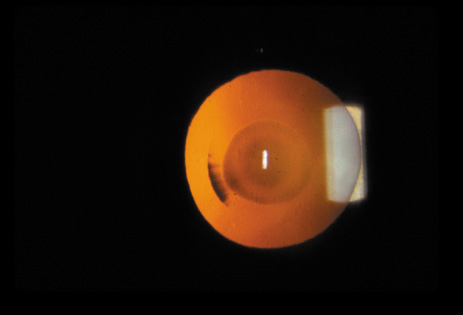

Nuclear cataracts tend to progress slowly. The refractive index of the lens changes as the nucleus progressively hardens, which usually results in increasing myopia.20,21 In some patients this is accompanied by optical distortion, especially of distant images, while near vision remains unaffected. A nuclear cataract is best seen with the narrow-beam direct illumination employed by the slit-lamp, which reveals the color and generalized haze or opalescence of the nucleus. In the early stages, the two halves (cotyledons) of the embryonic nucleus remain visible (Fig. 3). Later the entire nucleus appears as a homogeneous mass in contrast to the cortex (Fig. 4). Retroillumination may show the “oil droplet” effect (Fig. 5). Sometimes one may notice crystals in the lens nucleus (known as a Christmas tree cataract; Fig. 6A and B).

Fig. 3. Early nuclear cataract. Note the “cotyledons” in the nucleus.

Fig. 4. Advanced nuclear cataract. Note the homogeneous nuclear opacity.